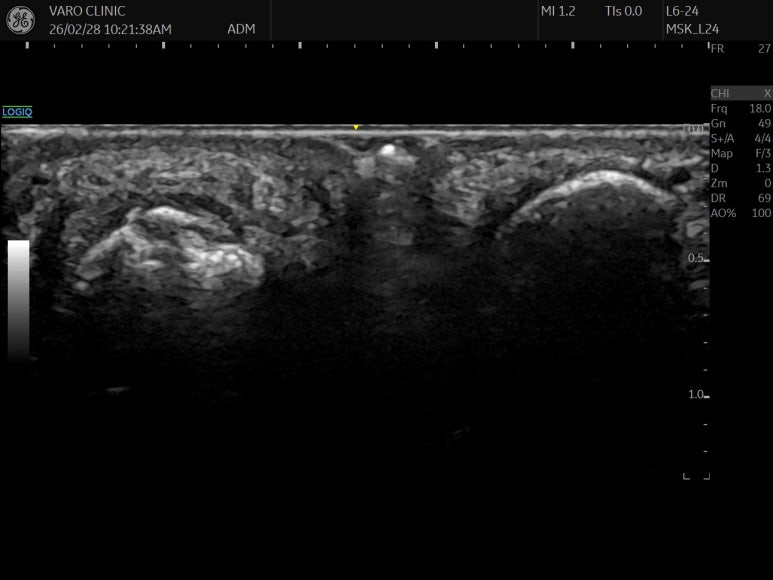

Step-off sign

네번째 발가락 골피질이 어긋나서 fracture of 4th middle phalanx

솟아오른 모습입니다.

다친 지 4주가 넘었는데

뼈 주변 골막 아래

피가 고여 있고(Hematoma)

주변 조직이 염증으로 부어있습니다.

위쪽 표준 경혈 초음파와 비교해보면

확연히 다른게 보이시죠?

프로브를 90도 돌려서

단축 스캔했을 때에도

골절(骨折)이 의심됩니다.